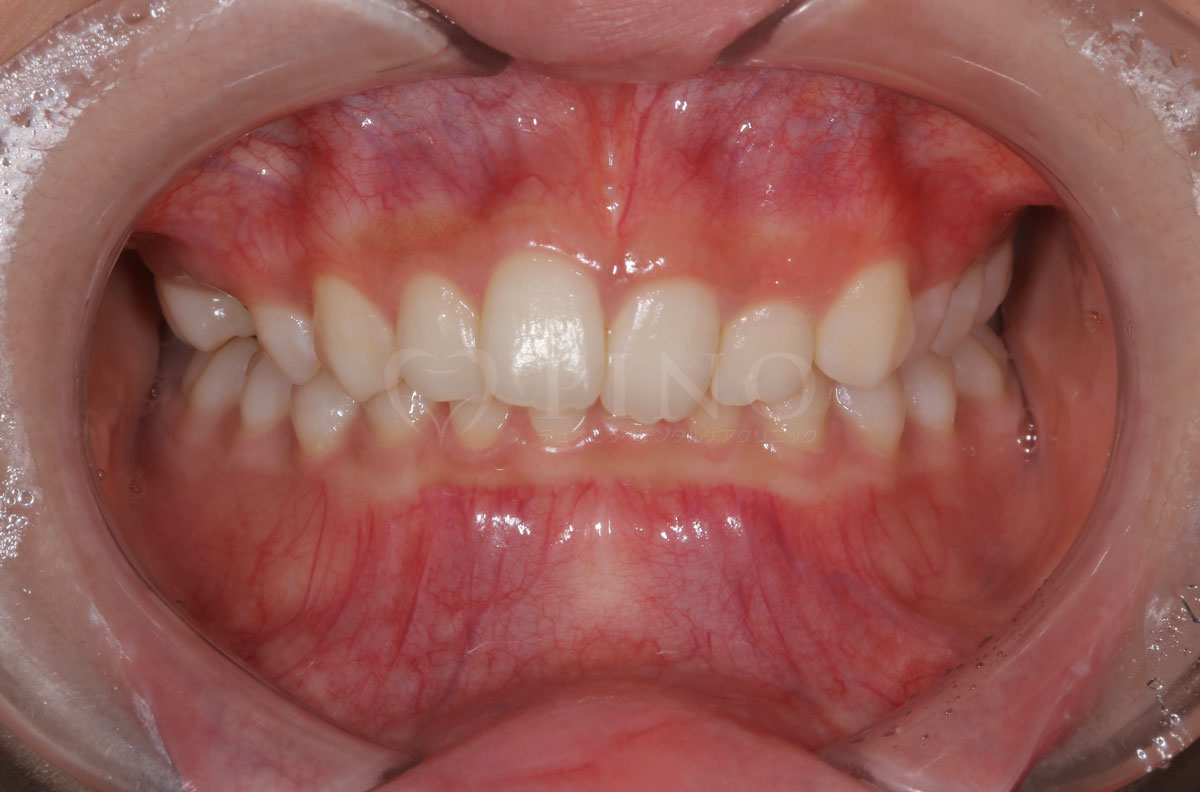

症例4:噛み合わせが深く、下の歯が見えないのが気になる(10代女性)

主訴 噛み合わせが深い、下の歯が見えない 診断名 過蓋咬合(かがいこうごう) 治療方法 マウスピース全顎矯正 抜歯 なし オルソパルス なし 治療期間 1年1ヶ月 費用 746,000円 副作用・注意点 矯正後の後戻りを防ぐためリテーナーの使用が必要となる -